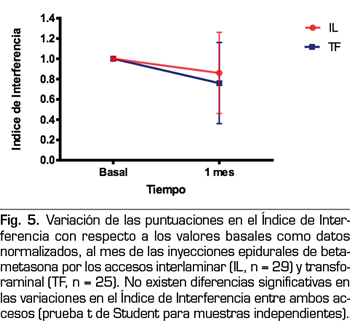

Los Índices de Intensidad e Interferencia también fueron reducidos por la inyección epidural de esteroides (Figuras 4 y 5). La betametasona administrada por la vía interlaminar parasagital redujo el Índice de Intensidad de 7,2 ± 1,2 a 5,8 ± 2,1 y el Índice de Interferencia de 7,0 ± 1,8 a 5,8 ± 2,5, en ambos casos una disminución estadísticamente significativa (p = 0,002 y p = 0,01, respectivamente; prueba t de Student para muestras pareadas). La betametasona administrada por la vía transforaminal redujo el Índice de Intensidad de 7,7 ± 1,6 a 5,7 ± 2,4 y el Índice de Interferencia de 7,7 ± 1,7 a 6,3 ± 3, reducción estadísticamente significativa (p = 0,0002 y p = 0,008, respectivamente). No hubo diferencias estadísticamente significativas entre ambos accesos al comparar la reducción de ambos índices.